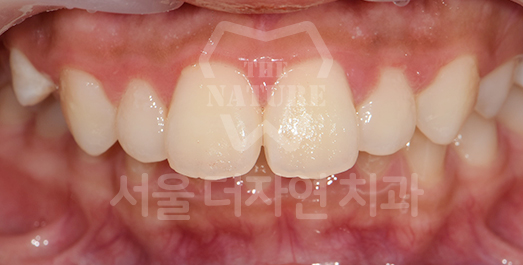

Diastema (Spacing) Solution

We first diagnose whether the spacing is generalized throughout the dentition or localized to specific areas such as the anterior teeth. Treatment involves attaching orthodontic appliances and

moving the teeth into the vacant spaces to achieve proper alignment.

• BEFORE: 2020.11.12

• AFTER: 2023.04.06